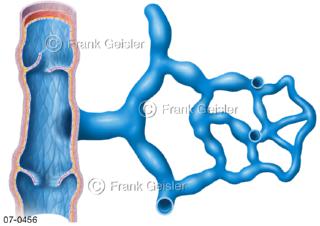

Bildergalerie Herz, Blutkreislauf

Bilder zu Herz, ein muskuläres Hohlorgan, das den menschlichen Körper durch rhythmische Kontraktionen mit Blut versorgt und dadurch die Durchblutung der Organe sichert, das Kreislaufsystem zeigt den Transport von arteriellem sowie venösem Blut durch das kardiovaskuläre System (Herz-Kreislauf-System), bestehend aus Blutgefäßen, Lymphgefäßen und dem Herz